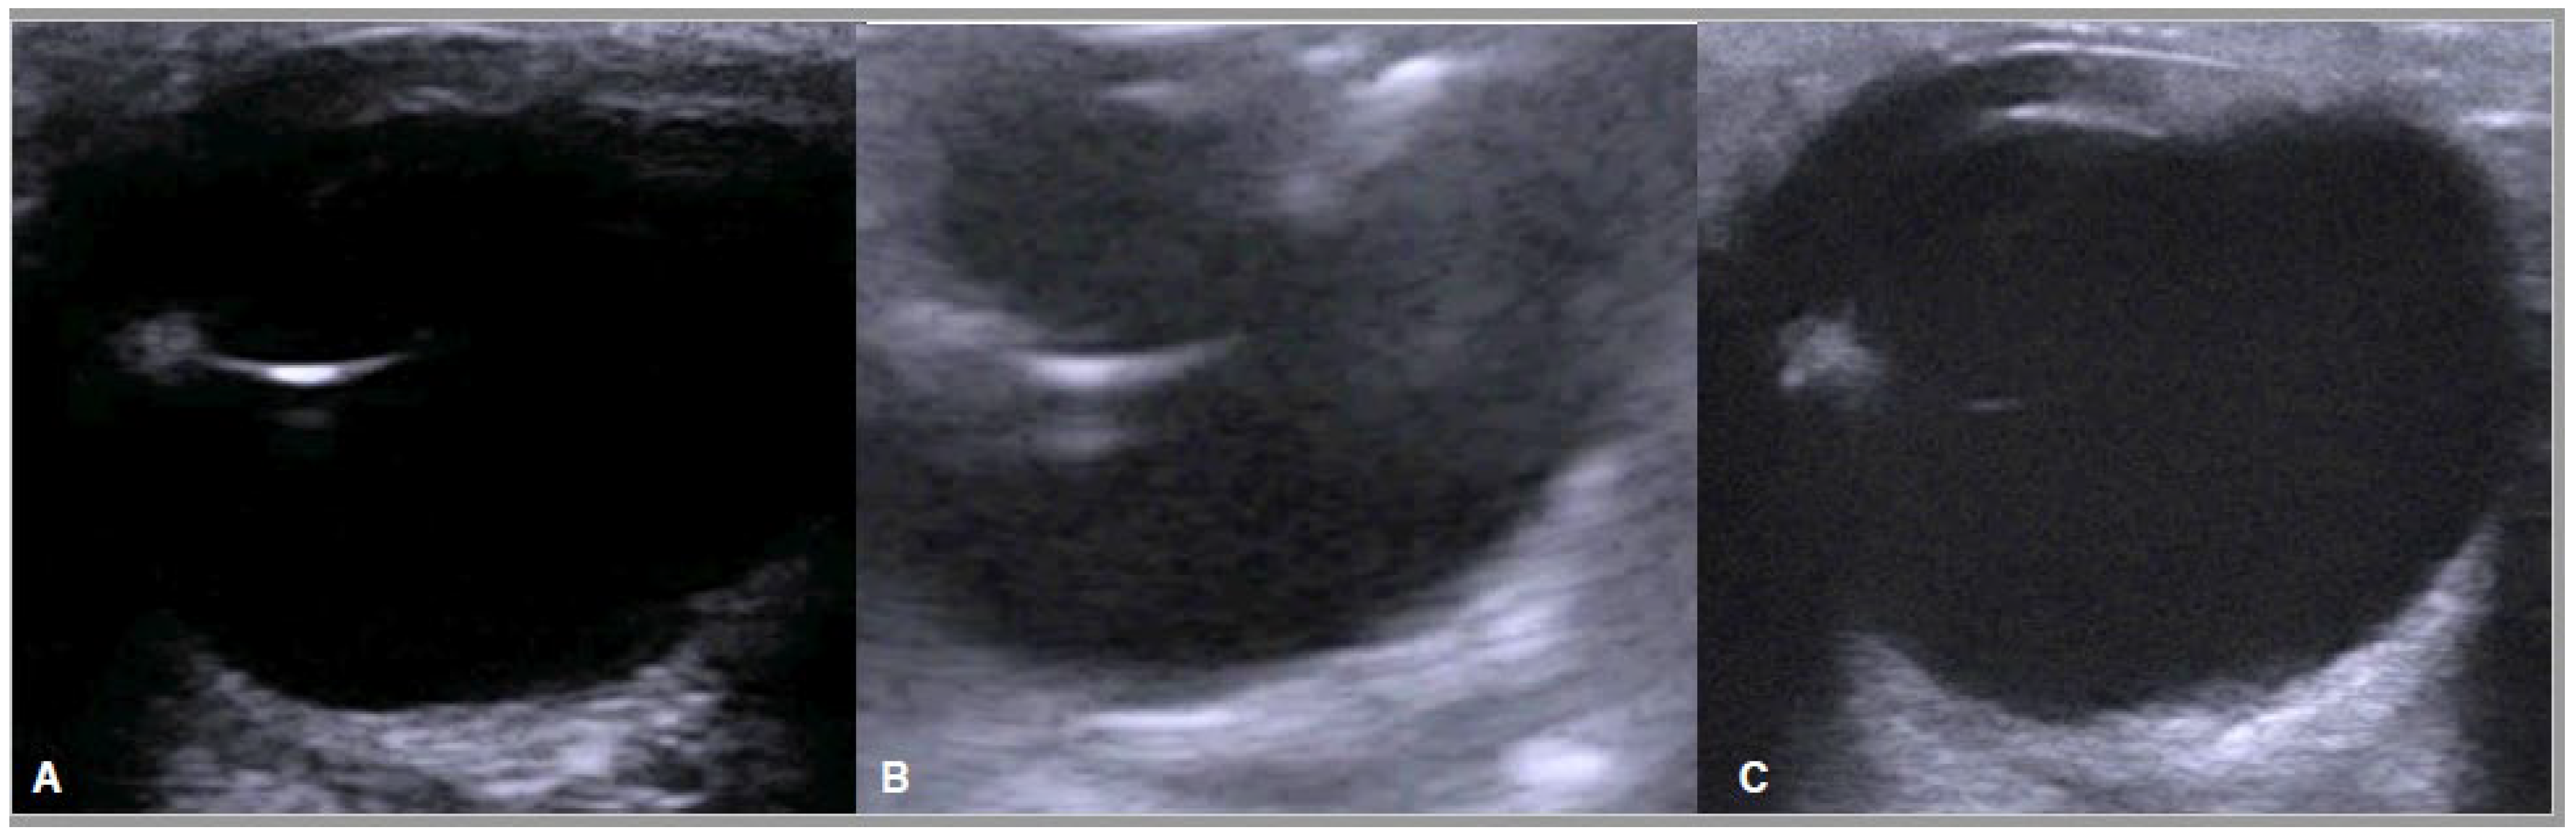

- Potter, T.J.; Hallowell, G.D.; Bowen, I.M. Ultrasonographic Anatomy of the Bovine Eye. Vet. Radiol. Ultrasound 2008, 49, 172–175. [Google Scholar] [CrossRef] [PubMed]